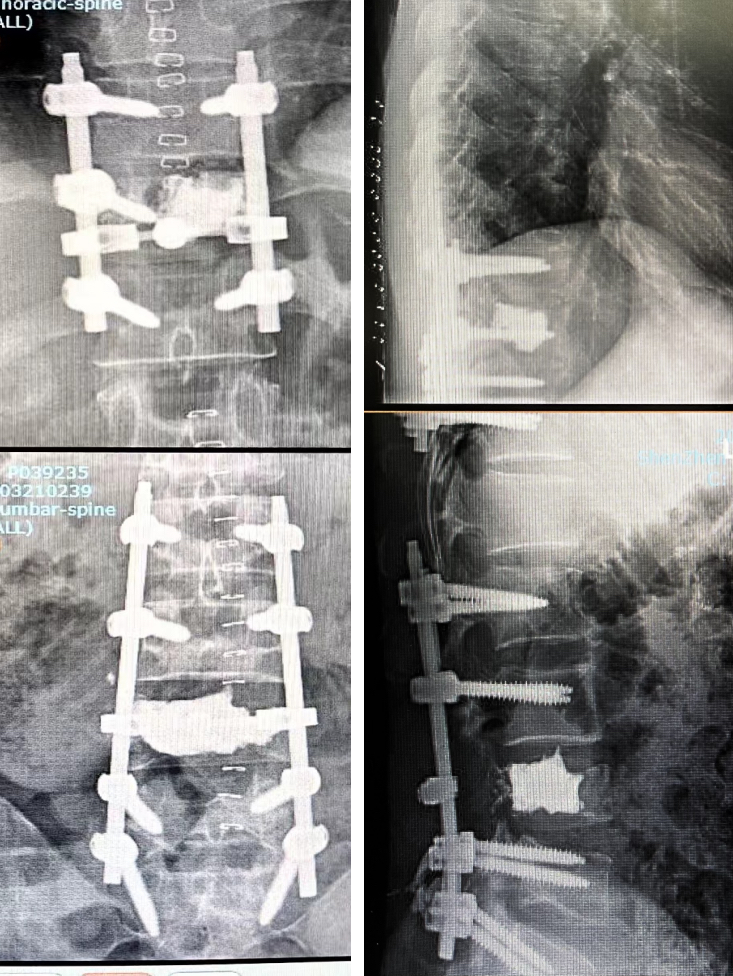

影像学检查如下:

术前一天行介入下栓塞;次日行T11、L4节段分离手术,胸椎短节段固定(移动窗、小切口),腰椎长节段固定(间隙固定),术中出血量不足1000ml。

术中及术后影像: